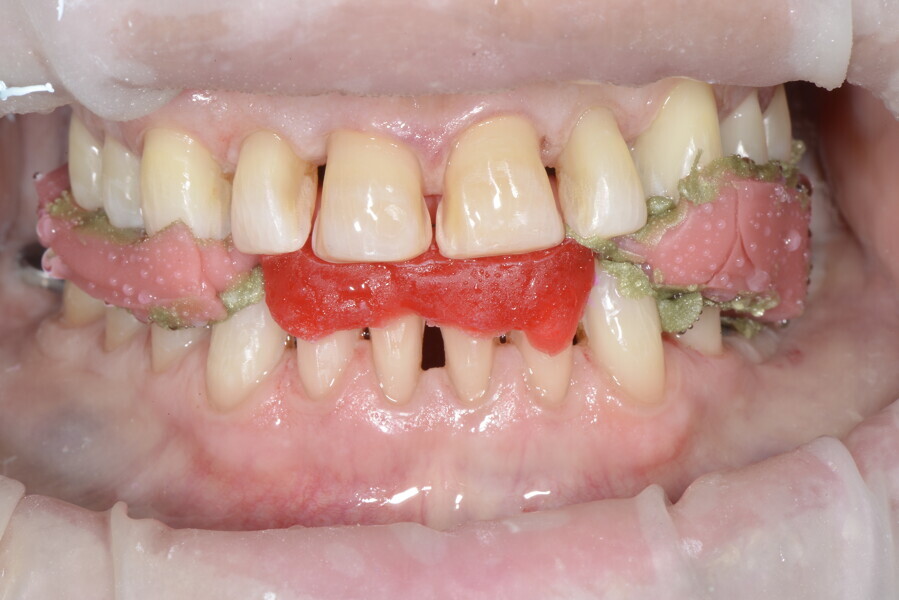

The 58-year-old patient wished to improve his oral aesthetics and function, complaining of mobility of the posterior teeth and wear of the anterior teeth. After data collection, a very complex situation was identified (Figs. 11–13):

1. severe periodontitis with poor prognosis of some teeth;

2. anterior crossbite;

3. severe wear mainly of the anterior teeth and compensatory eruption;38

4. atypical swallowing and lower posture of the tongue at rest;

5. masticatory dysfunction during the mastication test; and

6. no significant signs of temporomandibular disorder.

During the first visit, we checked the centric relation with cotton rolls, eliminating the posterior mesialising precontact and then performed a direct composite aesthetic and functional mock-up in this new position, not only to motivate the patient regarding the final result but also to help him understand better overall why tongue therapy, tooth alignment and dental resurfacing for augmentation of the vertical dimension of occlusion were required (Figs. 14 & 15).